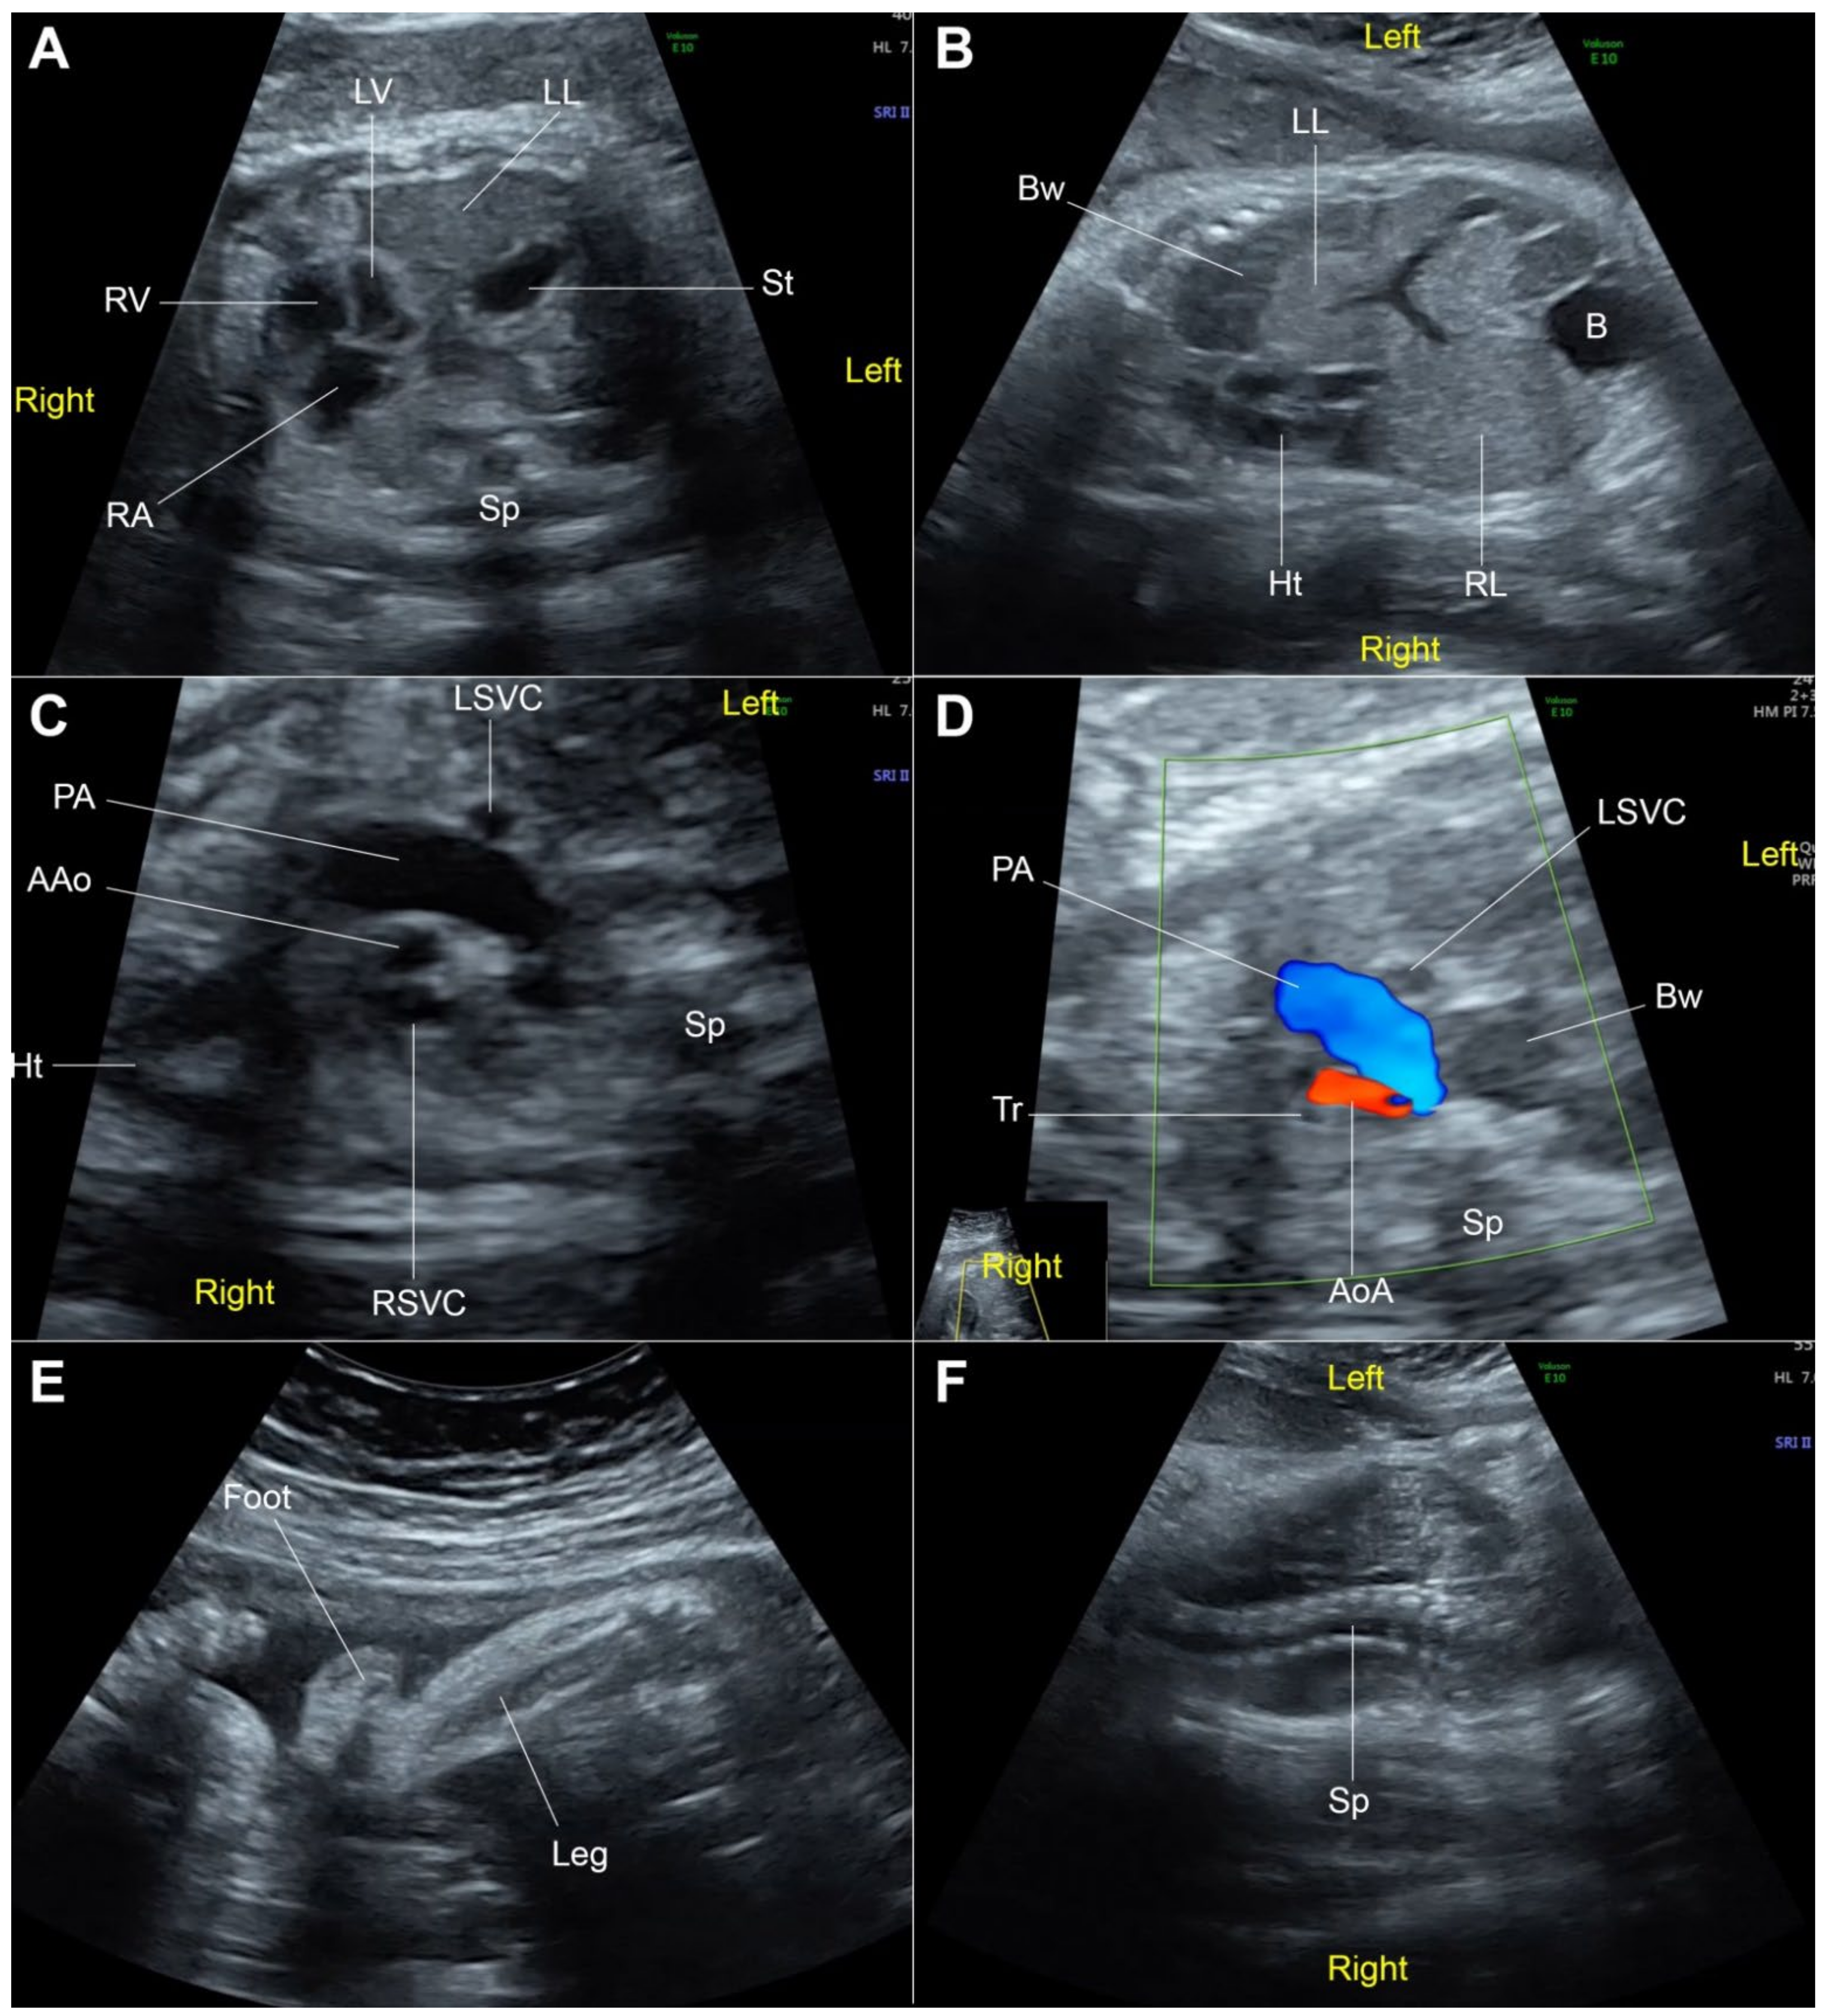

2. Case Presentation

| Present case (2022) | 30 | 32 | FGR CDH Low-set ears Hypoplastic aorta | Delivery (36 weeks) Stillbirth |